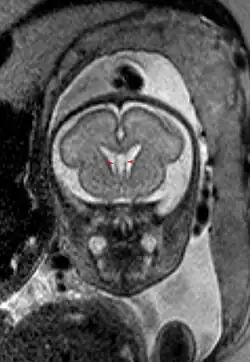

Размер полости крайне вариабелен, у некоторых полость полностью закрыта, в то время как у других отмечается практически полное её незаращение (до 46 мм в корональной плоскости).[3]

Собственно полость прозрачной перегородки расположена на уровне основания передних рогов боковых желудочков мозга, а её распространение в заднем направлении в область тел боковых желудочков выделяют под названием полость Верге (лат. cavum vergae). Во время эмбрионального развития происходит закрытие полостей в задне-переднем направлении, из-за чего персистирование полости Верге при закрытой полости прозрачной перегородки встречается значительно реже.

Полость прозрачной перегородки существует у 100 % эмбрионов человека, однако более чем в 85 % случаев она закрывается к возрасту 3-6 месяцев.[4][5]